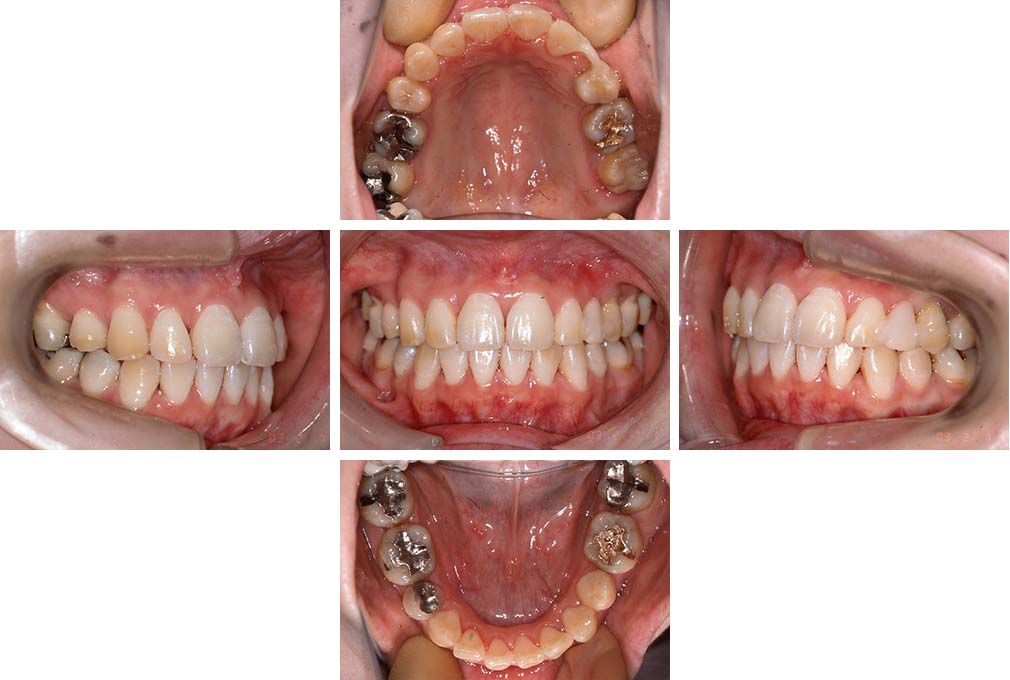

CASE:01

叢生を伴う骨格性上顎前突

初診時年齢 15歳10カ月

性別 男性

治療費の目安 約75万円程度(治療開始時)

上顎前歯の前突と叢生を主訴として来院された。大臼歯関係は左右側ともにⅡ級で上顎の方が前方に位置していた。叢生を伴う骨格性上顎前突と診断し、上下顎小臼歯抜歯を行っていただきマルチブラケット装置に顎外固定装置を併用して動的治療を行った。顎外固定装置や矯正用ゴムの使用など協力状態も良好で、動的治療期間2年0カ月、調整来院20回でマルチブラケット装置を撤去し保定へ移行した。動的治療終了後10年0カ月を経過したが保定移行時とほぼ同様の咬合状態で良好な状態を保っていた。

治療前

15歳10か月

治療後

動的治療期間2年0カ月

18歳5か月

10年経過

動的治療終了後10年0カ月

28歳5か月